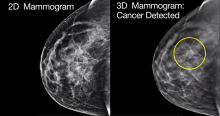

Seno Medical Instruments, Inc., the company pioneering opto-acoustic imaging as a tool to improve the process of diagnosing breast cancer, today announced preliminary information from a feasibility study of its Imagio breast imaging device. Results from the feasibility study suggest that information from Imagio, beyond that available from traditional breast ultrasound, may be helpful in assisting physicians in their decisions whether to recommend biopsies for women with suspicious breast masses. The data were presented at the annual meeting of the Radiological Society of America (RSNA).